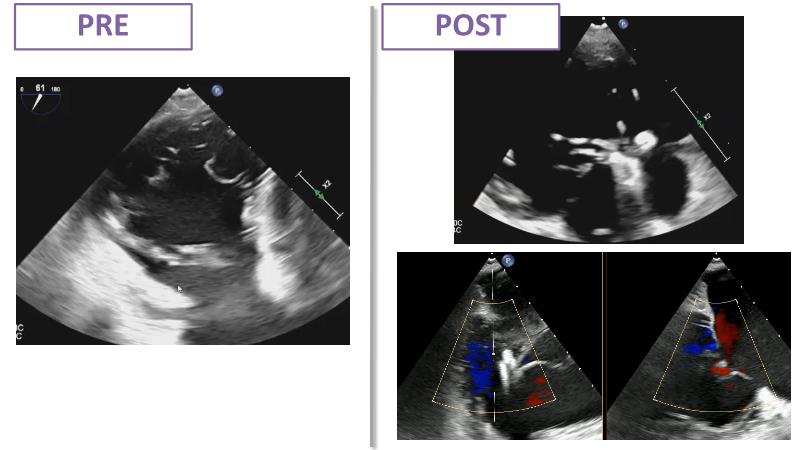

Based on an in-depth review of the data from TRILUMINATE pivotal, a randomized trial whose findings were recently published in the NEW ENGLAND JOURNAL of MEDICINE, this lecture explains how these results will impact clinical practice in the treatment of tricuspid regurgitation. Join the speakers and learn more.

- To understand why it is key to intervene in tricuspid regurgitation disease - A safe option for an unmet need

- To learn how TRILUMINATE Pivotal - the first randomised trial - is impacting the clinical practice in tricuspid regurgitation treatment

- To understand how the broadest body of evidence supports TriClip therapy as first line treatment option for tricuspid regurgitation